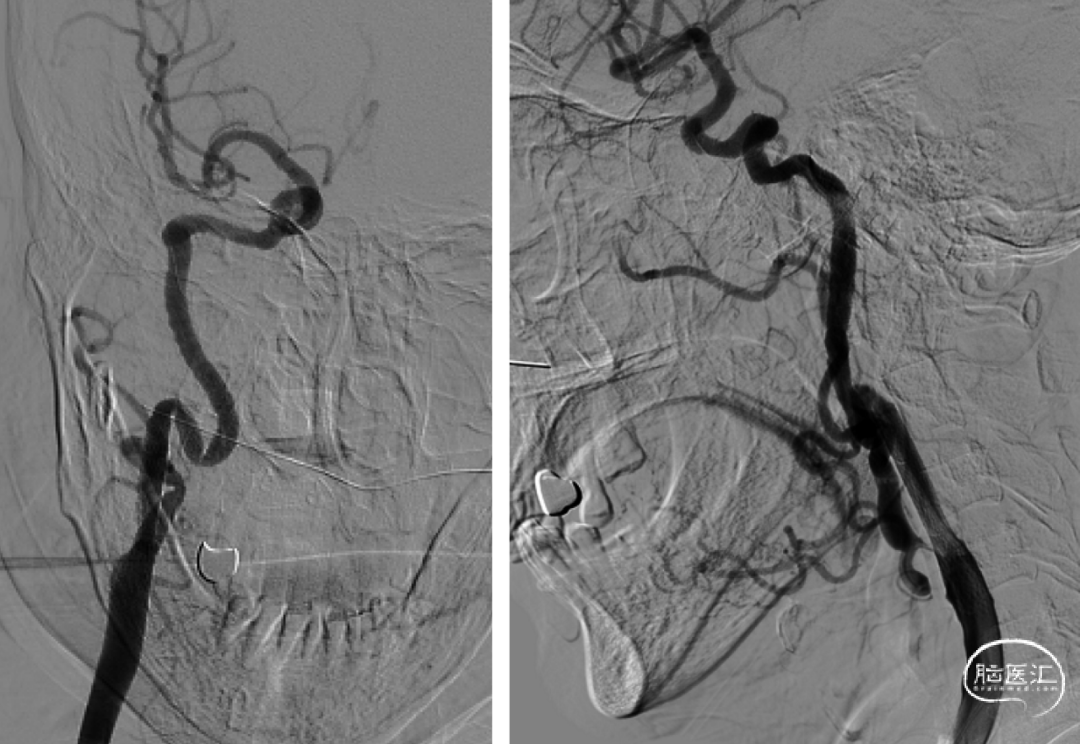

双侧颈总动脉、双侧锁骨下动脉造影,右侧颈总动脉正侧位、双侧斜位造影提示:右侧颈内动脉起始部重度狭窄,狭窄率99%。颈内动脉C1段非常迂曲。

术前分别进行左右侧颈内动脉及椎动脉正侧位造影。可见右侧颈内动脉起始段重度狭窄,病变远端有延迟血流通过,左侧颈内动脉造影可见前交通开放良好。